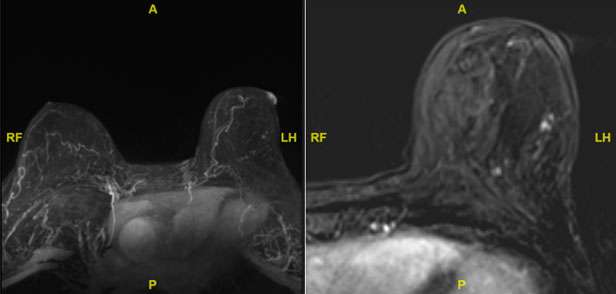

The mammographic findings of Paget’s disease include skin thickening in the nipple areolar complex region, nipple retraction, underlying suspicious calcifications, or a discrete mass. The ultrasound findings include nonspecific heterogeneity of the breast parenchyma, a mass, dilated ducts, and skin thickening or hypervascularity in the nipple areolar complex (Figure 3). Breast MRI may assist in further evaluation in the setting of negative mammogram and ultrasound findings (Figure 4).

WU: Skin Change Figure 4

Figure 4. Same patient as in Figure 2. Dynamic contrast enhanced MRI was performed for evaluation of a primary breast malignancy in the setting of a negative mammogram and ultrasound. The left MIP image demonstrating abnormal right nipple enhancement compatible with biopsy proven Paget’s disease. The right subtraction image demonstrates a focus of non-mass enhancement measuring slightly less than 3 cm at 2 o’clock, mid-to-posterior depth, and extending anterior to the pectoralis muscle (BI-RADS 4B). MRI-guided biopsy subsequently confirmed ductal carcinoma in situ.